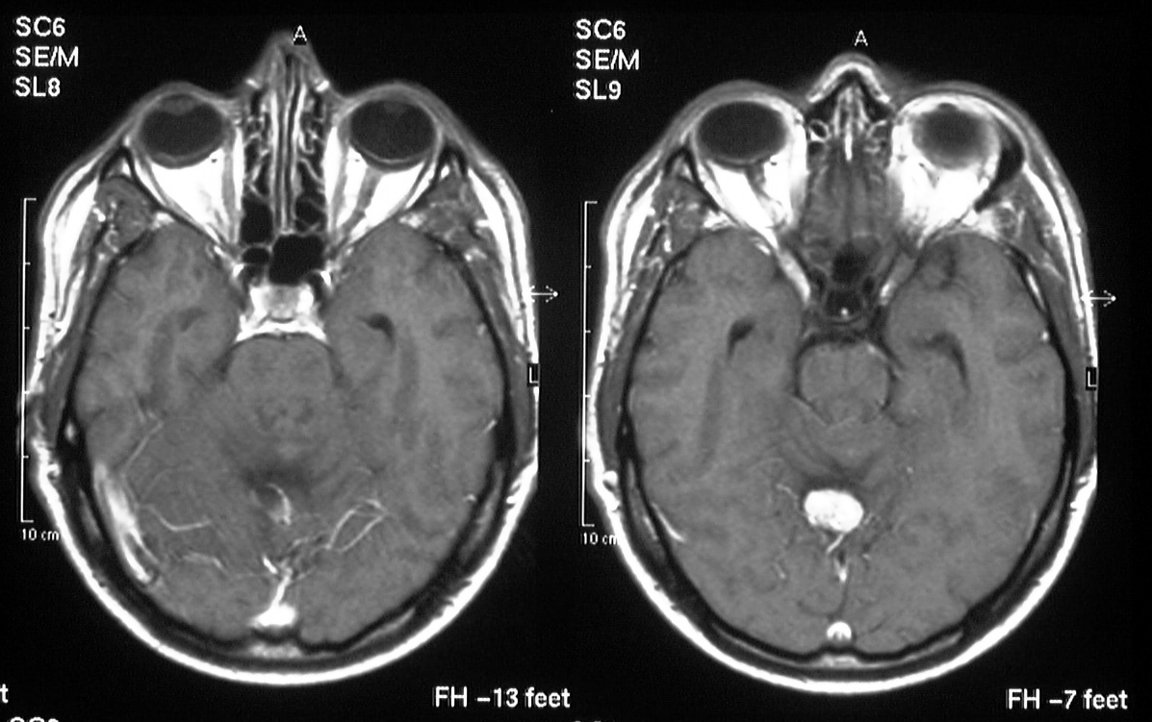

Von Hippelova-Lindauova choroba (skratkou VHL) sa radí medzi vrodené ochorenie, ktoré je spájané s viacerými tumormi v rôznorodých orgánoch. VHL - asociované tumory zahŕňajú hemangioblastómy (nádory vzniknuté zo spleti kapilár v mozgu, miechy a retiny). Tumory sietnice, retinálne angiómy vedú s úplnej strate zraku, ak nie sú liečené. Pacienti s VHL majú vyššie riziko vzniku svetlobunkového karcinómu obličiek, pankreatického neuroendokrinného tumoru (pNET), vznik feochromocytómu a tumoru nadobličiek.

Ak má lekár podozrenie na VHL mutáciu, definitívnu diagnózu stanoví pomocou genetického molekulárneho testovania. Podozrenie na VHL mutáciu majú lekári v prípade majú pacienti viaceré hemangioblastómy mozgu a miechy, retiny, alebo jeden hemangioblastóm a zároveň karcinóm obličky, pankreatické cysty, endolymfatické cysty vaku, alebo epidymálne cysty alebo iná kombinácia týchto benígnych alebo malígnych tumorov.

Terapia sa riadi liečebnými protokolmi pre každý tumor zvlášť. Management by mal zahŕňať celoživotné sledovanie oftalmológom, MRI mozgu, CT brucha, laboratórne testy. Rizikoví príbuzní by mali byť zahrnutí do skríningového vyšetrenia už od detstva, aby sa zamedzilo neskorej diagnostike a vzniku metastáz nádorov. Karcinóm obličiek je najčastejšou príčinou smrti, ďalšou býva hemangioblastóm mozgu.